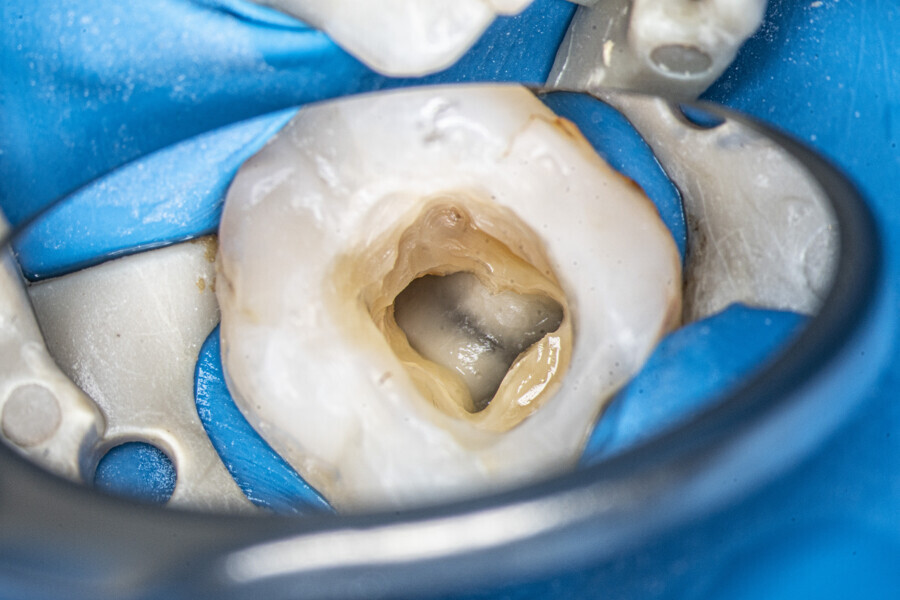

The first trials of the LPE concept were performed on extracted human molars. Although the dynamics of fluid during root canal irrigation are completely different in vivo than in extracted teeth, these kinds of trials provide initial information about the procedure. Some of these teeth had apices closed with a coat of wax and composite resin to close the apical delta and simulate the periapical tissue. After creation of the access cavity, the pulp chamber was cleaned with continuous irrigation with 5.25% NaClO activated with a SkyPulse laser (Fotona) in AutoSWEEPS mode (20 Hz, 15 mJ). A 25/0.07 reciprocating file (Shenzhen Perfect Medical Instruments) was used to perform the pre-flaring procedure. After opening the coronal third, continuous irrigation with 5.25% NaClO activated with the laser was used to clear the debris for 30 seconds. After removing the debris, a #10 C-PILOT file (VDW) was used to establish apical patency, without forcing the file if possible. In some cases, apical patency was reached already at this stage of root canal preparation. In all cases, the second step of instrumentation was the preparation of the middle third with the same file, and the same irrigation procedure was performed. Subsequently, the C-PILOT file was used to reach the apical foramen. At this stage, apical patency was reached in most cases, but in some roots, there was no possibility of entering the apical foramen. The working length was confirmed with a radiograph with the hand file. Usually, the next procedure to be done is apical preparation, but the LPE concept is based on an enhanced irrigation protocol. Following this protocol, irrigation was performed for 5 minutes with continuous flow of 5.25% NaClO activated with the SkyPulse laser in AutoSWEEPS mode (20 Hz, 20 mJ) with a conical sapphire fibre. The next step was alternating irrigation with 17% EDTA for 30 seconds, with 5.25% NaClO for 30 seconds and with 17% EDTA for 30 seconds, all activated with AutoSWEEPS, followed by irrigation for another 5 minutes with 5.25% NaClO activated with AutoSWEEPS. In most cases, the next step after this stage of enhanced irrigation was the calibration of the apical constriction rather than apical preparation per se, but this step requires further investigation.

At the first appointment, both teeth were opened, the old restorations were removed, all the root canal orifices were located and the first mesiobuccal (MB1), distobuccal (DB) and palatal canals were shaped. In both teeth, the MB2 orifices were located, but the canals were not shaped. The preparation phase was similar to that explained earlier. During the root canal preparation phase, the hand file was used to establish patency after each reciprocating instrument, and the canals were flushed with NaClO activated with the SkyPulse laser in SWEEPS mode for 10–15 seconds. After reaching two-thirds of the estimated working length with the reciprocating files, the LPE enhanced irrigation protocol with the SkyPulse laser was employed. The apical preparation was not performed at this stage. Owing to a lack of time at this appointment, the canals were flushed with EDTA and sterile water, and a 2% solution of chlorhexidine was poured as an intra-canal dressing. Both teeth were closed with temporary composite restorations.

At the second appointment, the temporary restorations were removed, and the chlorhexidine was washed out with sterile water and EDTA. After opening the orifice of the MB2 canal in the first molar, the operator was not able to reach patency in the canal. Therefore, the isthmus between the MB1 and MB2 orifices was opened with diamond-coated ultrasonic tips. Finally, patency was reached. Shaping the MB2 canal in the second molar was possible only to the place of the junction with the MB1 canal. The CBCT imaging had revealed previously that the MB2 canal should have its own lumen in the apical third, but the place of the junction was below the curvature. The possibility of locating this space without damaging the root was very poor. At this stage, the LPE enhanced irrigation protocol was performed again. After performing of the irrigation protocol, the apical preparation was performed for all the canals. The final irrigation protocol was performed with 5 minutes of constant flow of 5.25% NaClO for 2 minutes, alternating with 17% EDTA for 30 seconds, with 5.25% NaClO for 30 seconds and 17% EDTA for 30 seconds, and irrigation with 5.25% NaClO for 5 minutes. All the irrigants were activated with an EDDY sonic tip (VDW). After performing the periapical radiographs, a CBCT scan was performed to confirm the separate path of the sealer that filled previously unprepared spaces of the MB2 canals in both teeth. In both cases, it was clearly visible on the CBCT image that all the previously unprepared spaces were filled with the obturation material.